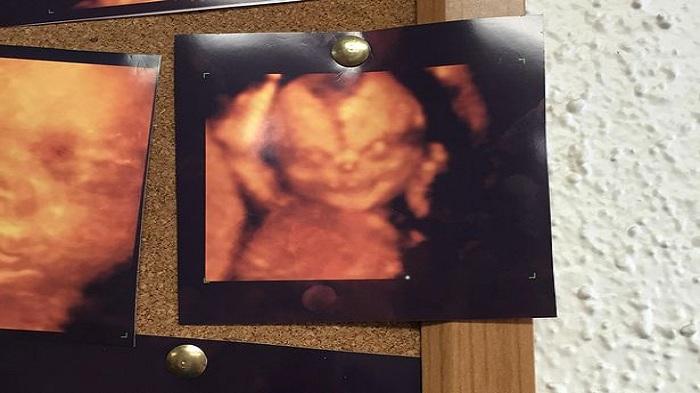

Foto USG 4D Janin Ini Membuat Takut sang Orangtua

BANJARMASINPOST.CO.ID - Hasil pindai ultrasonografi empat dimensi (USG 4D) terhadap janin mereka membuat orangtua mereka ketakutan.

Pasalnya, seperti dilaporkan seorang pengguna Reddit berinisial itsallrelative yang dikutip Mirror, Sabtu (15/8/2015), foto yang dihasilkan menampakkan wajah yang menyeramkan.

"Dan istri saya pergi untuk mendapatkan USG 4D, dan usai melihat anak kami yang belum lahir membuatnya berubah pikiran,” tulis itsallrelative.

Foto USG 4D yang dipajang memperlihatkan sosok berwajah sinis dengan tatapan matan yang menyeramkan.

Namun beberapa netizen menganggap kalau foto tersebut telah mengalami distorsi sehingga tercetak hasil foto yang kasar dan tidak menampilkan wajah sebenarnya dari sang janin.

"Ini adalah gambar di papan pengumuman di ruang tunggu. Rupanya itu seharusnya untuk menegaskan kembali keputusan saya. Jelas tidak. Dan istri saya pergi untuk menjalani USG ‘tradisional’,” ungkapnya.